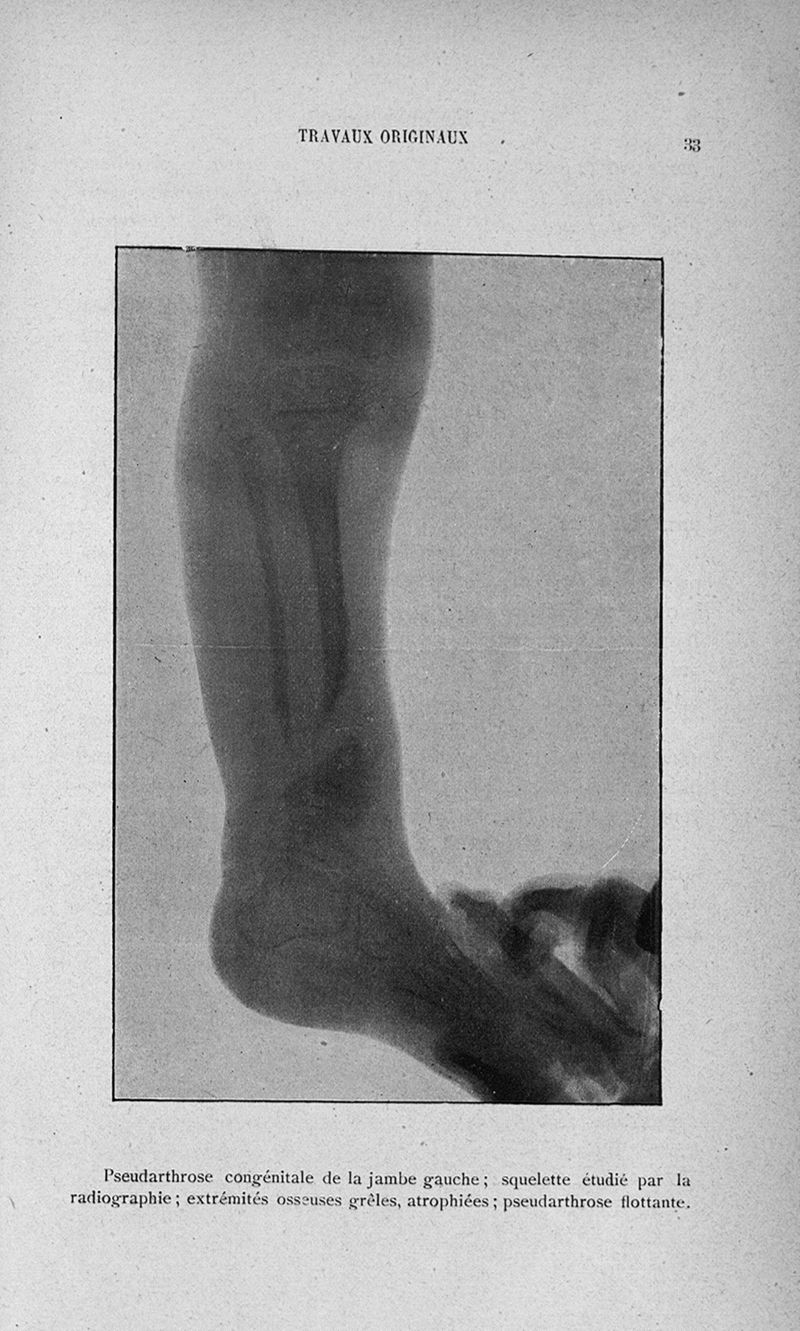

URL pérenne de cette page : https://www.biusante.parisdescartes.fr/histmed/medica/page?110133x031x32&p=33